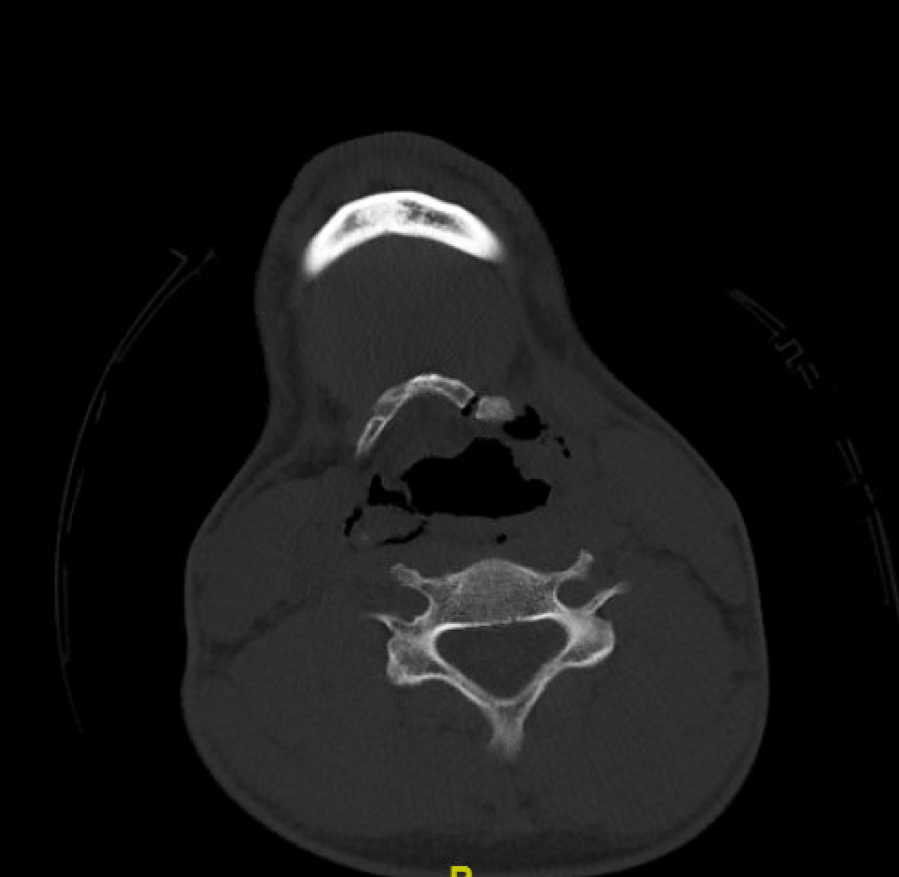

Figure 1: Non-contrast portion of the CTA neck.

CT imaging reveals a left hyoid bone fracture, as well as a comminuted fracture of the right thyroid cartilage. His CTA is normal. He has no intracranial injuries, face or C-spine fractures. There is considerable soft tissue emphysema.